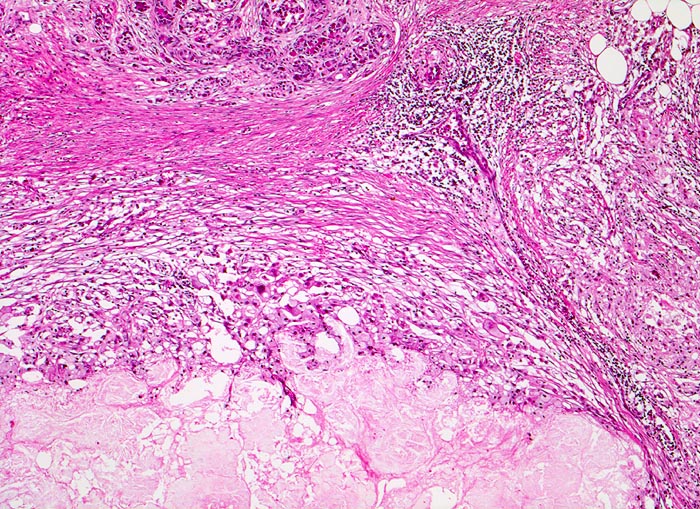

Je nach Ursache der chronischen Pankreatitis unterscheidet sich das Muster der Fibrose. Die Nekrosen des interlobulären Gewebes und der interlobulären Gänge bei ethylischen Pankreatitisschüben führen primär zu einer interlobulären Fibrose und interlobulären Gangstrikturen. In den betroffenen interlobulären Gängen führt der Sekretstau zur Konkrementbildung (verkalkte Proteinpräzipitate). Wie bei einer chronisch obstruktiven Pankreatitis kommt es in den unvollständig drainierten Läppchen zu einer Atrophie der Azini verbunden mit intralobulärer Fibrose. Letztere Areale enthalten schliesslich nur noch Reste unregelmässig verteilter Gänge, Inseln, Nerven und Gefässe. In vielen Fällen lassen sich extrapankreatische Pseudozysten gefüllt mit nekrotisch-hämorrhagischem Detritus in der Nachbarschaft der fibrosierten Bezirke nachweisen. Ein Tumor (> 2066), eine Narbe oder einen Stein können als Folge einer Obstruktion des Pankreasganges im Pankreaskopf eine diffuse Atrophie und Fibrose des Pankreas nach sich ziehen. Diese Form wird als chronische obstruktive Pankreatitis bezeichnet und ist gekennzeichnet durch eine deutliche poststenotische Dilatation des betroffenen Pankreasganges ohne Konkrementbildung und eine diffuse Fibrose des an den obstruierten Gang angrenzenden Parenchyms. Bei einer Schädigung des Gangepithels und der Gangwände wie bei hereditärer oder Autoimmunpankreatitis entwickelt sich primär eine periduktale Fibrose. Im Gegensatz zum duktalen Adenokarzinom ist das erhaltene Parenchym bei der chronischen Pankreatitis lobulär angeordnet. Drüsenepithelien zeigen keine Atypien. Karzinomverdächtig sind irregulär infiltrierende atypische Drüsen, atypische Drüsen in unmittelbarer Nachbarschaft von grösseren Gefässen ohne dazwischenliegende Azini, Perineuralscheideninvasion, rupturierte oder inkomplette Drüsen, und Drüsen mit luminalem nekrotischem Detritus.

• Erhaltene Läppchenarchitektur.

• Breite Bänder von sklerosiertem zellarmem Bindegewebe verlaufen zwischen den Läppchen.

• Atrophie des exokrinen Pankreas.

• Erhaltene Inseln und Gangstrukturen.

• Spärliches chronisches Entzündungsinfiltrat.

• Rechts oben ist eine partiell vom Rand her durch Granulationsgewebe organisierte lytische Fettgewebsnekrose erkennbar. Diese ist Folge eines akuten pankreatitischen Schubs.